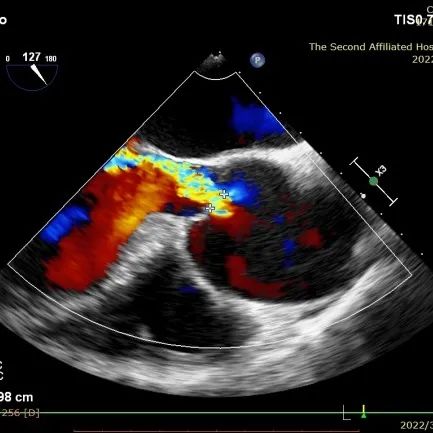

术中影像监护与评估(DSA&TEE)

DSA和TEE显示无瓣周漏,瓣膜位置、形态良好

DSA和TEE显示J-Valve瓣架形态、位置良好,瓣叶开放活动度正常,收缩期前向血流通畅。术后一天患者精神状态良好。